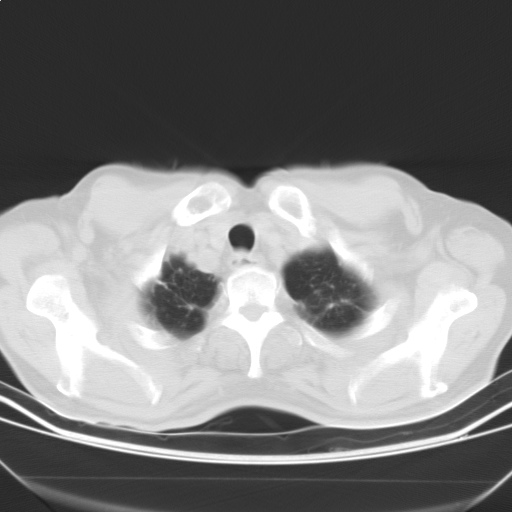

以下是引用随光逐影在2009-5-1 13:53:00的发言:[br]考虑为:1)两肺血行播散型肺结核;2)右肺下叶炎症感染。3)右侧胸膜增厚。